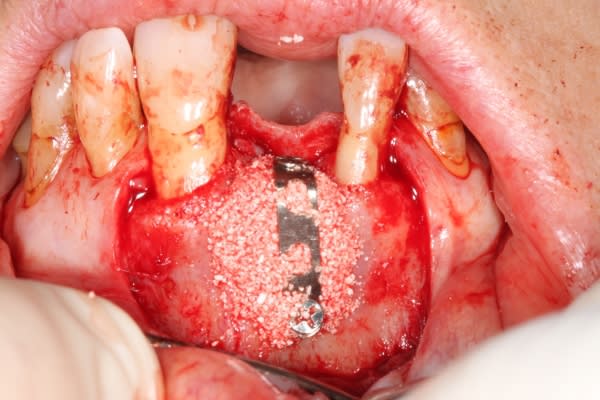

Extraction implantation immédiate mais il y a au moins 7 spires à nue... (photo 1, 2)

dans cette technique un pilier de 2mm de haut est vissé sur l'implant, ce pilier contient un orifice qui permet de transfixer la barre (photo 3,4)

l'espace créé est rempli avec un biomat et le tout est recouvert d'une membrane